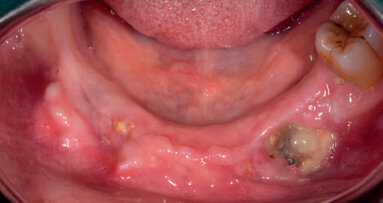

Il paziente P.F. di anni 74 si presenta all’attenzione della Fondazione Istituto Stomatologico Toscano con osteonecrosi della porzione distale dell’emimandibola di sinistra (Fig. 1). Il quadro clinico del paziente, dal punto di vista anamnestico, appare da subito piuttosto complesso. Il paziente, infatti, è affetto da diverse patologie: insufficienza renale cronica; idronefrosi dilaterali; pregressa emicolectomia destra per etp; diverticolosi del colon residuo; enfisema polmonare; portatore di CVC tipo port.

Come evidenziato nella documentazione fotografica iniziale, la quantità di tessuto necrotico esposto risultava essere molto estesa. Inoltre, il paziente presentava in prima visita suppurazione dei tessuti interessati dalla necrosi, con edema accentuato dell’emivolto di sinistra. Si è deciso di procedere con intervento chirurgico nel marzo 2014 (Fig. 2) con l’obbiettivo di asportare il tessuto osseo necrotico e promuovere in un secondo momento, con l’ausilio del PRF (Fig. 3), la guarigione dei tessuti circostanti. A 7 giorni venivano rimossi i punti di sutura (Fig. 4) e a 14 giorni il paziente veniva richiamato per una visita di controllo: in tale occasione era stata osservata esposizione di una porzione tissutale ossea, complicanza per altro attendibile nei trattamenti con bifosfonati (Fig. 5). È stato deciso pertanto di inserire il paziente nel protocollo di ozonoterapia per favorire e promuovere guarigione secondaria. Si osservavano, fin dalle prime sedute di applicazione del protocollo di ozonoterapia, dei significativi miglioramenti, in particolare del versante vestibolare della lesione.